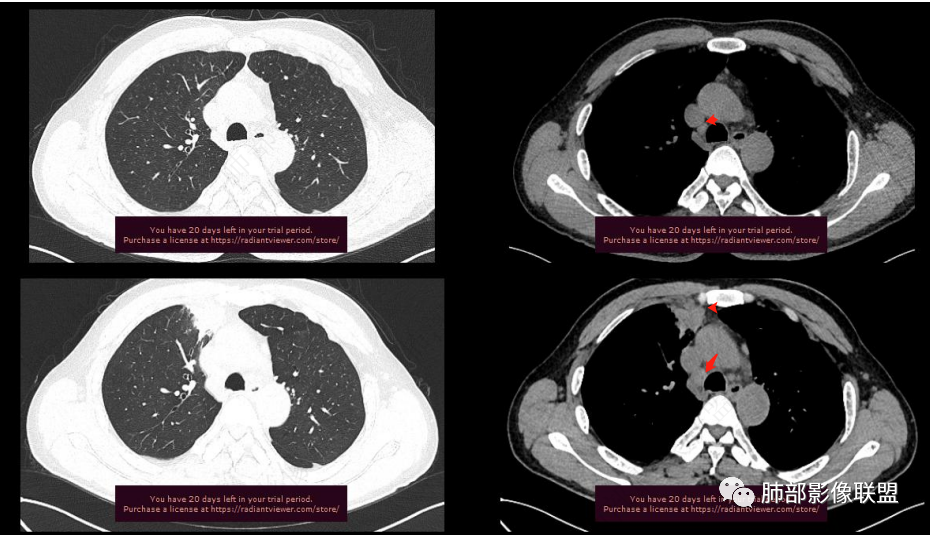

增大淋巴结

很多增大的淋巴结,强化方式一致均匀,

未见明确坏死,融合不明显,没有明确的分布优势。

肝脏病变明确,是轻度强化,延迟强化特点,边缘模糊,有轻微的包膜挛缩。

2.右肺上叶纵隔旁新发实性密度病灶,密度均匀,轻度强化,未见空洞、液化坏死及钙化,血管穿行自如,支气管进入后狭窄截止。灶周磨玻璃影边界不清,病灶未见明显分叶毛刺,平直、轻度收缩、周围偶见结节影,但未见树芽征。注意纵隔胸膜侵入或突入比较明确。纵隔淋巴结轻度增大。

4.肝脏病灶没有假包膜,没有动脉早期强化,没有肝硬化,未见扩张胆管,未见环形强化,也未显示靶征,缺乏肝细胞肝癌、胆管细胞癌、转移癌或肝脓肿特征。

但回顾性分析,如此少血供确实可以符合淋巴瘤,如果密度更均匀一点的话,这是我们有所忽略的地方。

5.淋巴瘤可以解释影像改变,但仅凭影像及临床很难想到它是霍奇金!结外病变主攻方向以肝组织、肺组织为主,还突破胸膜?